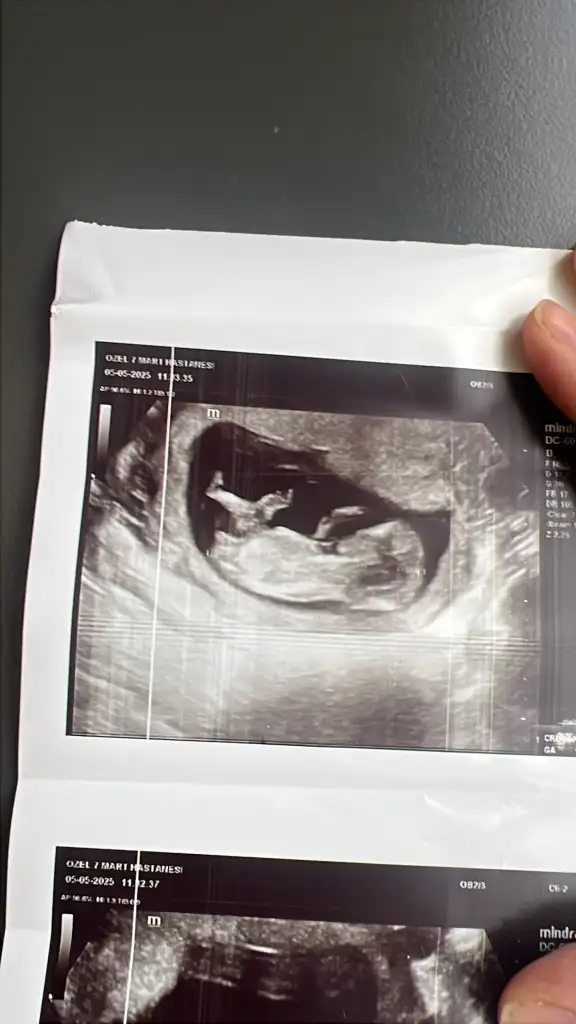

Ay hadi inşallah bir oğlum var birde kız olur inşallah şuan 12+2 haftalık 14 haftada gidecem sonucu sizede yazarımAy canım benim Allahım gönlüne göre versin ama nubu belli olmuyor ne desem yalan olur ha yine de içimden kız geçti sağlıkla gelsin![]()

Merakla bekliyoruz annesiAy hadi inşallah bir oğlum var birde kız olur inşallah şuan 12+2 haftalık 14 haftada gidecem sonucu sizede yazarım![]()

Kız gibi geldiSizce ne cinsiyeti

Doktorda erkeğe benzettiKız gibi geldi

DoğrudurDoktorda erkeğe benzetti